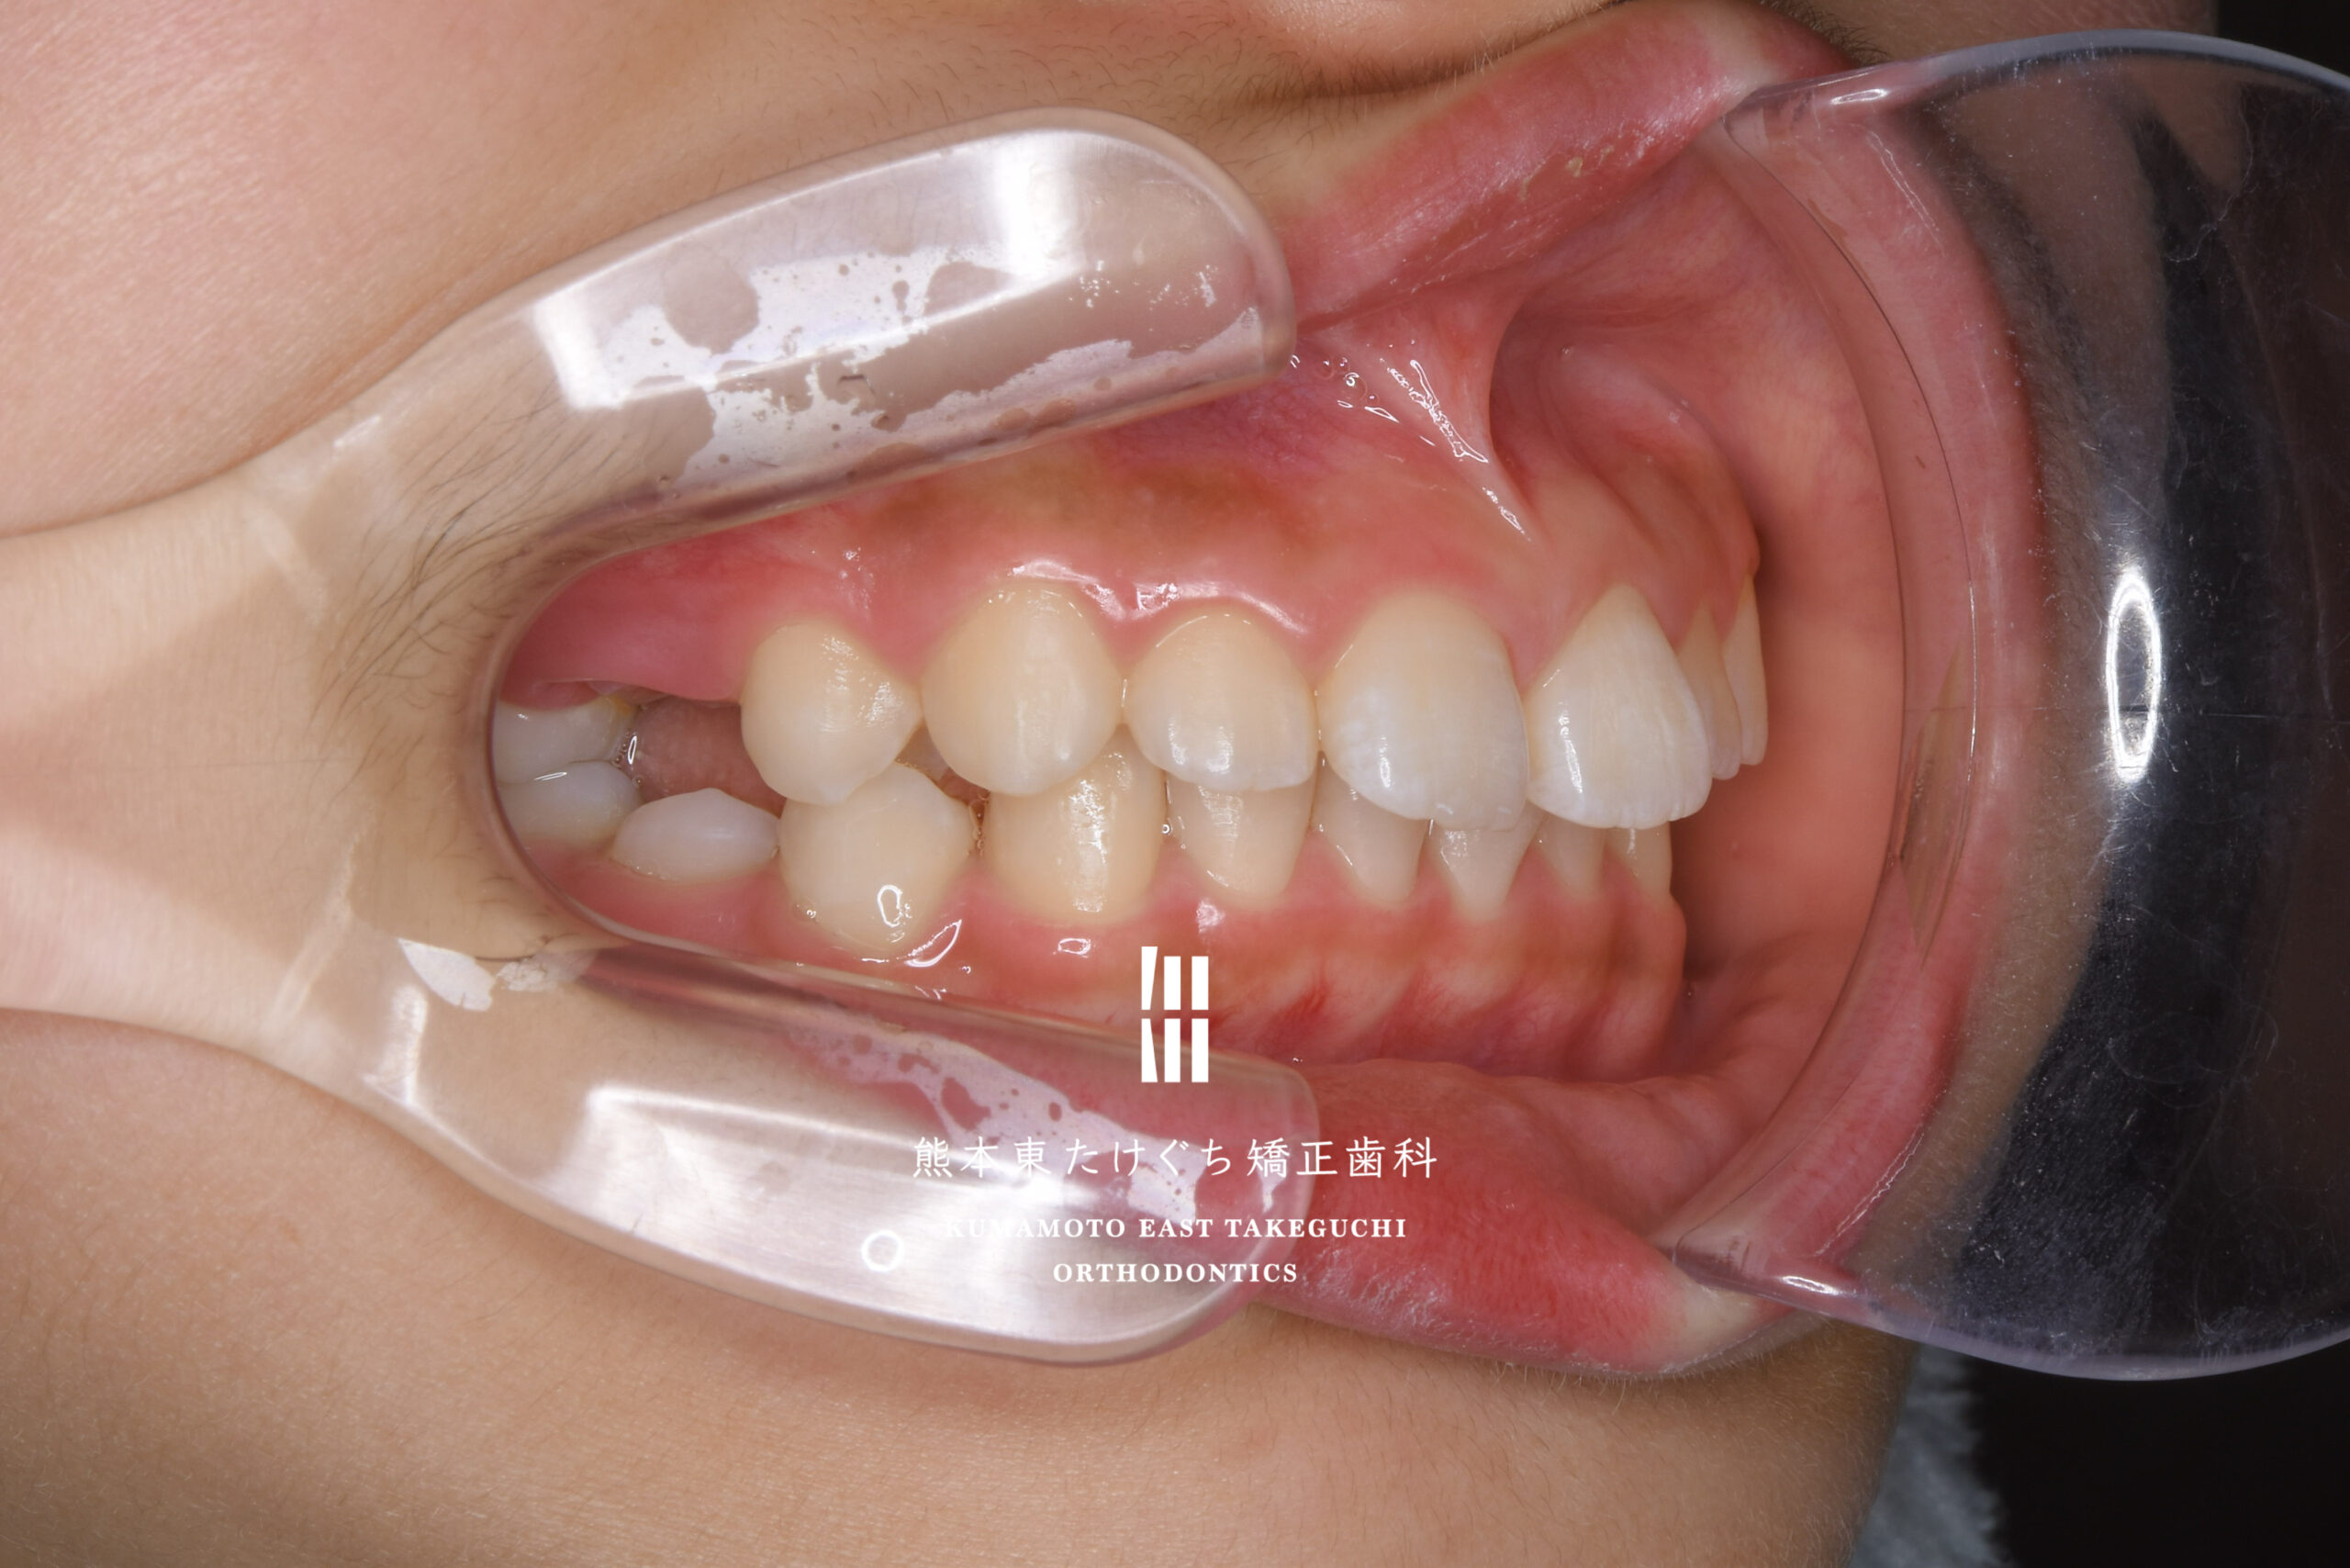

9歳女児 小児矯正 すきっ歯 かみ合わせが深い 出っ歯

治療内容 正中離開および過蓋咬合を伴う上顎前突を改善するため、取り外し式の矯正装置 BJA(バイト・ジャンピング・アプライアンス)と、部分的固定式ワイヤー装置を用いて治療しました。